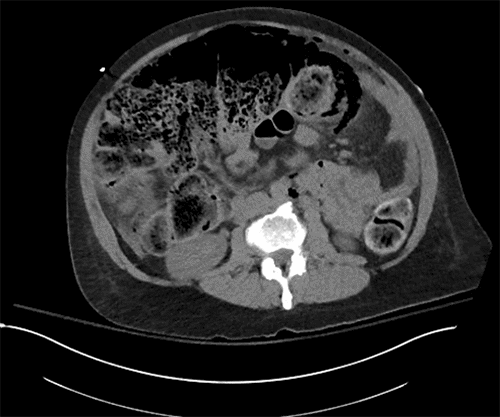

The patient’s condition deteriorated, marked by increasing lethargy, tachycardia, and worsening abdominal signs and symptoms, including peritonitis. Following discussion with maternal-fetal medicine, a CT scan of the abdomen and pelvis was performed, revealing free air and stool in the abdomen (Figure 1). Given these findings, an emergency laparotomy was planned in conjunction with the obstetrics team, with continuous perioperative fetal monitoring.

Figure 1. Abdominal and Pelvic CT Imaging (Axial and Coronal Views) with IV Contrast. Published with Permission

The axial view demonstrates a large fecal burden with associated air trapping

The coronal view confirms significant fecal impaction with multiple air pockets, suggestive of stercoral perforation